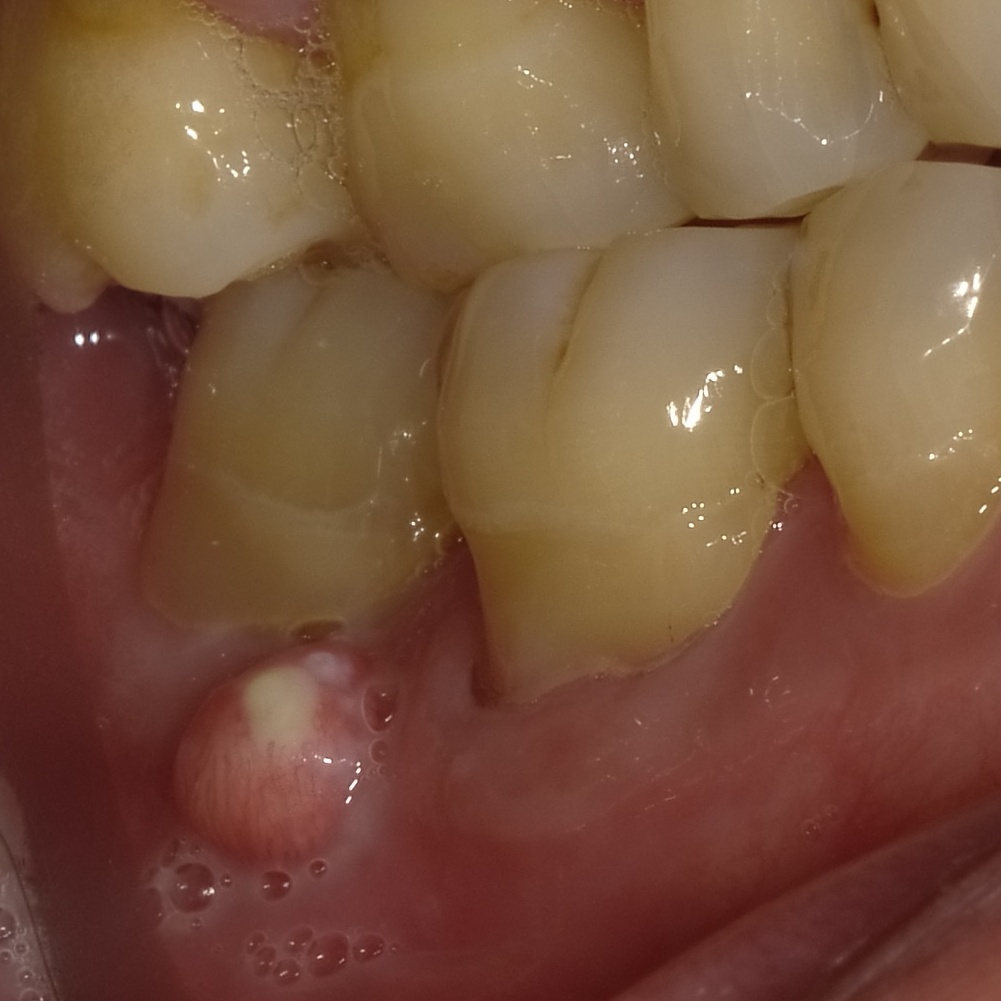

写真は歯茎にできたできもの(サイナストラクト)です。